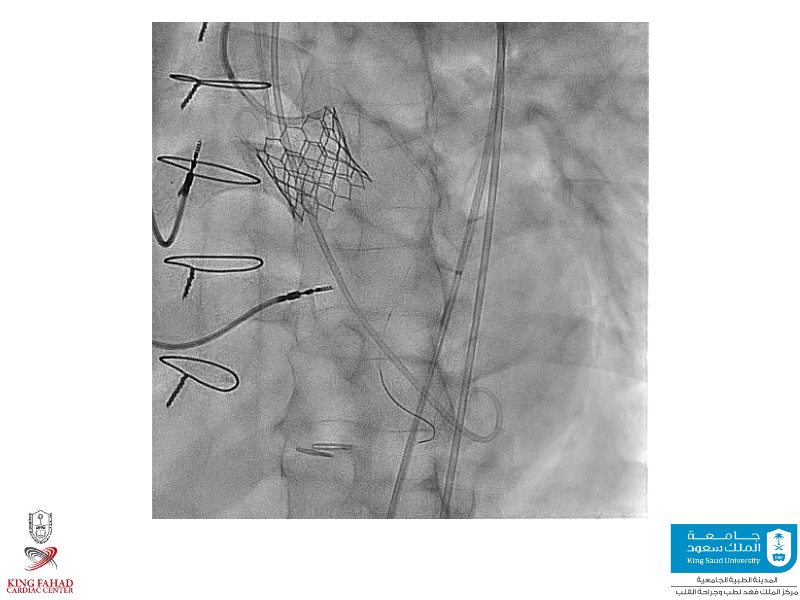

Second valve strategies with SAPIEN 3 Ultra RESILIA

This session helps you anticipate and address complex scenarios such as mitral valve-in-valve, TAV-in-SAV, and valve-in-valve-in-valve procedures. Learn from expert case discussions that explore procedural strategies, technical challenges, and best practices to optimize outcomes in redo structural heart interventions.